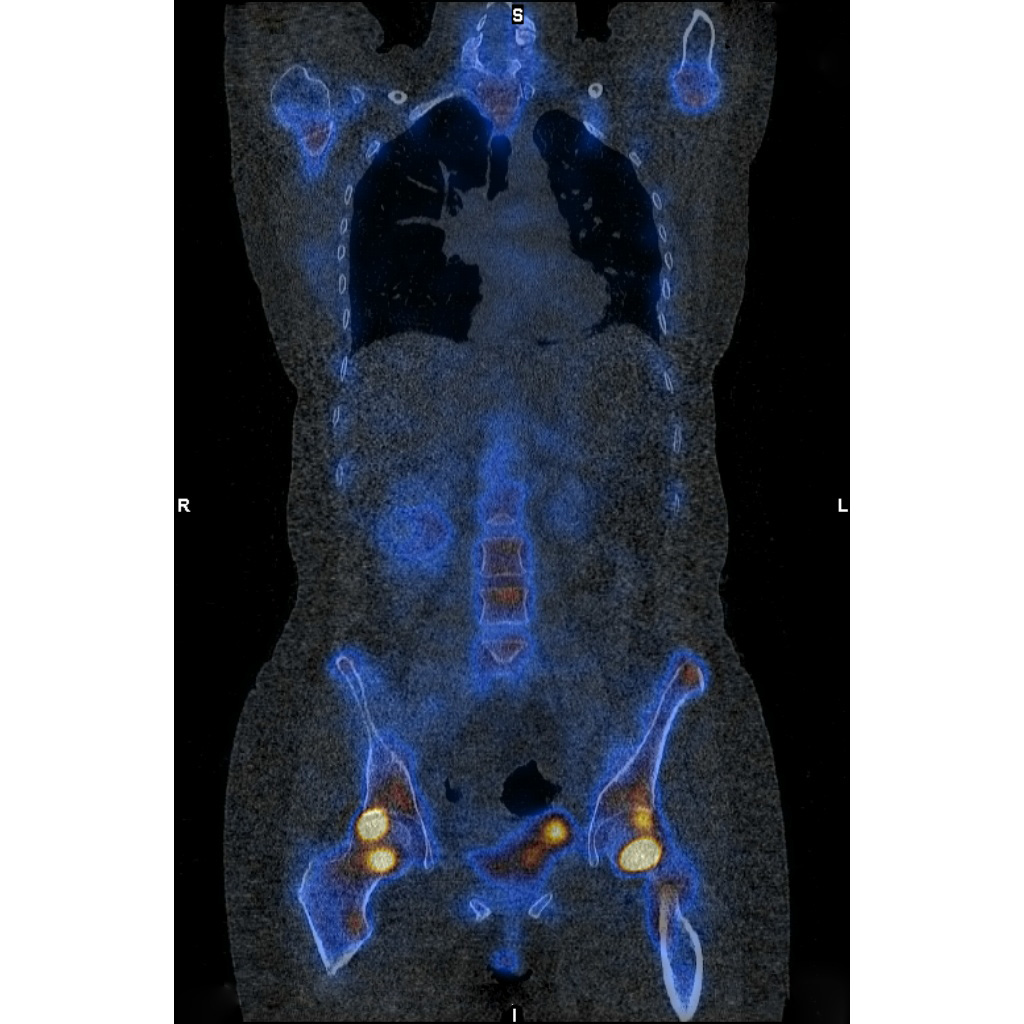

Der Effekt zeigt sich früh. Bereits innerhalb der ersten sechs Monate nach der Infusion steigt das Risiko. Es bleibt auch danach erhöht. Besonders häufig betreffen die Brüche die Hüfte oder das Becken. Typisch sind dabei auch sogenannte Ermüdungsbrüche, die sich schleichend entwickeln. „Eisencarboxymaltose war mit einem höheren Risiko für Knochenbrüche verbunden“, resümieren die Autoren der Studie.